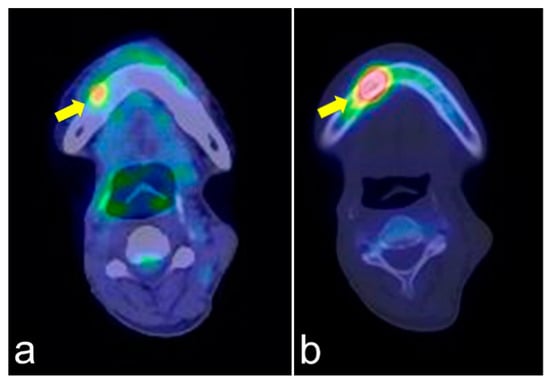

3.2. CT Findings

On CT images, homogeneous bone consolidation was observed in 10 (20.8%) patients. Heterogeneous bone consolidation was observed in 30 (62.5%) patients, and six (12.5%) patients showed bone resorption. Using pre-treatment CT data, we compared the levels of bone consolidation. The cancellous bone was sclerosed in 28 (58.3%) sites; however, eight (16.7%) sites did not show clear bone consolidation images, and one (2.1%) site clearly showed bone resorption. Eleven (22.9%) sites did not have sufficient data (Figure 1a,b). Moreover, the periosteal reaction was not observed in 44 (91.7%) sites, and the periosteal reaction was observed in four (8.3%) sites. At first, there were four pathological fracture cases during the observation period, and finally, there were six cases.

Figure 1.

Pre-treatment mandible on axial computed tomography (CT) scan (a) and osteoradionecrosis (ORN) mandible on axial CT scan (b). The image shows bony sclerotic changes with ORN (b) involving the right mandible compared to the pre-treatment mandible in the same lesion without periosteum reaction (arrowhead). These reactions may have been induced by irradiation.